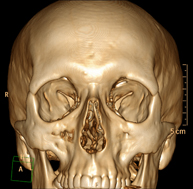

Prueba radiológica que consiste en obtener imágenes del macizo facial (cara) de alta definición anatómica mediante el empleo de un equipo de TC (Tomografía Computarizada). Indicaciones: tumores, cirugía plástica. - TC Oídos